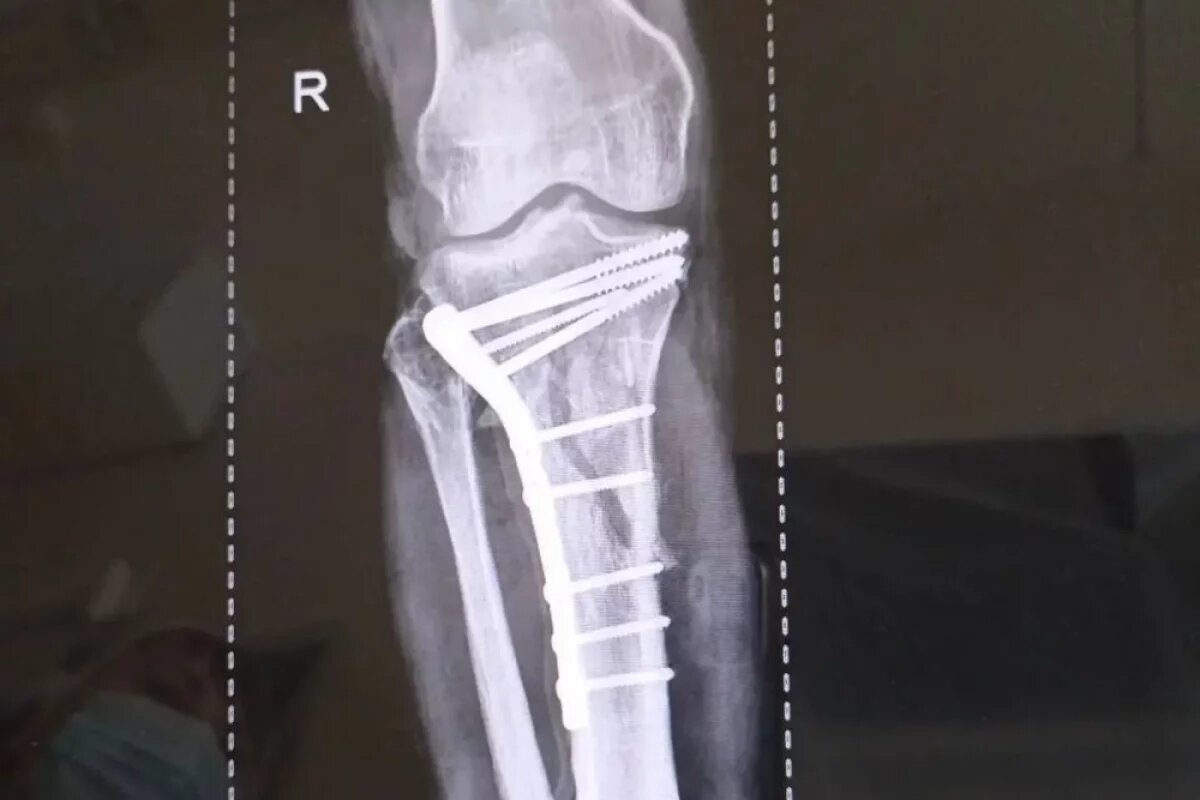

В Липецке врачи-травматологи горбольницы «Липецк — Мед» спасли ноги мужчины после серьёзного ДТП. Об этом сообщили в пресс-службе областного Минздрава. Пациент поступил после тяжелого ДТП 25 февраля. У него были внутрисуставные переломы верхних зон обеих голеней. Врачам потребовались почти три часа, чтобы по кусочкам собрать голени пострадавшего. Мужчина потерял довольно много крови, поэтому операция проходила на фоне хронической анемии. Оперировали заведующий отделением травматологии Дмитрий Соколов с ассистентом, врачом — травматологом Евгением Крюченковым. Специалисты оперировали одновременно обе ноги с минимальной кровопотерей. Сейчас пациента уже перевели из реанимации в отделение.

Пациент поступил после тяжелого ДТП 25 февраля. У него были внутрисуставные переломы верхних зон обеих голеней. Врачам потребовались почти три часа, чтобы по кусочкам собрать голени пострадавшего.

Мужчина потерял довольно много крови, поэтому операция проходила на фоне хронической анемии.

Оперировали заведующий отделением травматологии Дмитрий Соколов с ассистентом, врачом — травматологом Евгением Крюченковым. Специалисты оперировали одновременно обе ноги с минимальной кровопотерей. Сейчас пациента уже перевели из реанимации в отделение.